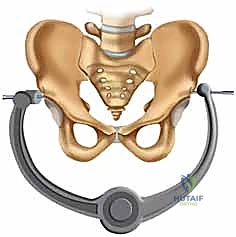

| طريقة العلاج | الراحة التامة في السرير لأسابيع، استخدام حزام الحوض (Pelvic Binder)، مسكنات الألم. | تدخل جراحي لرد العظام وتثبيتها ميكانيكياً باستخدام صفائح ومسامير معدنية. |

بمجرد استعادة الوضع الصحيح للعظام، يقوم الدكتور هطيف بتثبيتها باستخدام صفيحة معدنية متخصصة (غالباً صفيحة إعادة بناء متعددة الثقوب مصنوعة من التيتانيوم أو الفولاذ المقاوم للصدأ الطبي). يتم تثبيت هذه الصفيحة عبر المفصل العاني باستخدام مسامير قشرية (Cortical Screws) تُغرس بعمق في عظام العانة الصلبة لضمان تثبيت قوي يتحمل ضغط الجسم.